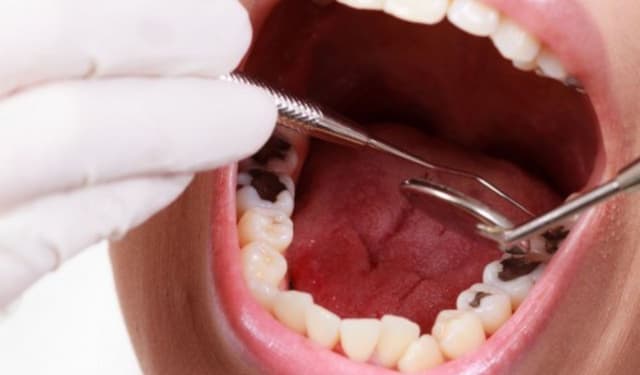

Răng bị sâu ăn: Dấu hiệu nhận biết và hướng xử lý kịp thời

Răng bị sâu ăn không chỉ gây đau nhức, khó chịu mà còn ảnh hưởng trực tiếp đến sức khỏe răng miệng và chất lượng cuộc sống. Nếu không được phát hiện và điều trị kịp thời, tình trạng này có thể dẫn đến viêm tủy, áp-xe răng hoặc thậm chí mất răng. Bài viết […]

Cách khắc phục sâu răng hiệu quả giúp hạn chế biến chứng

Cách khắc phục sâu răng là giải pháp quan trọng giúp bảo vệ sức khỏe răng miệng và hạn chế tối đa các biến chứng nguy hiểm như viêm tủy hay áp xe răng. Sâu răng vốn là một trong những vấn đề răng miệng phổ biến nhất hiện nay, ảnh hưởng nghiêm trọng đến […]